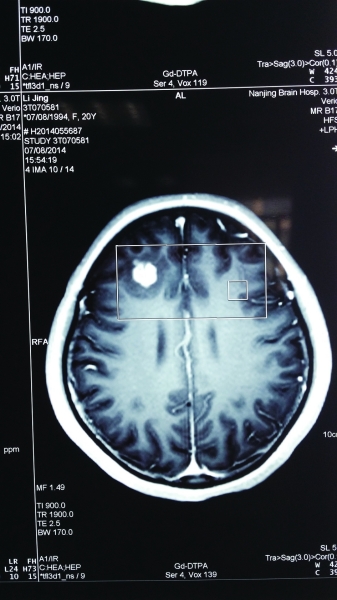

• 女孩脑中取出一条活的猪肉绦虫

孩脑中取出一条活的猪肉绦虫

CT扫描显示,小静脑中高亮处疑是寄生虫。来自淮安的20岁的女大学生小静(化名),因晕倒、抽搐等症状入院,起初都被当做癫痫治疗。南京脑科医院的专家,怀疑是寄生虫入脑,在手术当中,医生取出了一个3厘米长的白色虫子,放在托盘上的虫子还在动!据介绍.... [阅读全文] [我要评论]